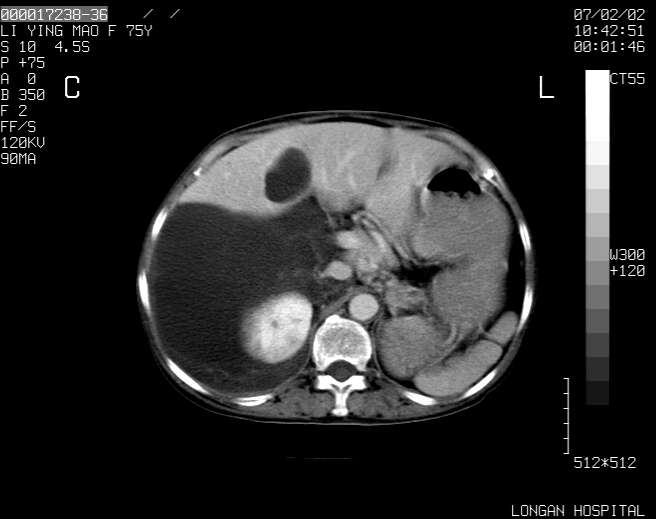

以下是引用dyqct在2007-2-10 8:53:00的发言:[br]考虑:1、肝脏多发囊肿[br] 2、左肾囊肿,右肾多发结石并积水。[br] 3、右胸少量积液。[br] 4、右肾周包裹性积液或淋巴管瘤(有见缝就钻的征象、薄隔、小结节状钙化)?[br] 5、腰椎动脉瘤样骨囊肿?[br] [br] [br]